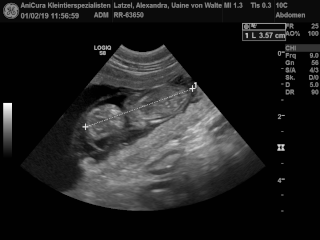

Sookie und Uaine erwarten Babies! Die Ultraschallbilder beweisen es! Hier sind die Bilder!!! |

| Die Ultraschallbilder von Uaine von Waltenweiler!!! |